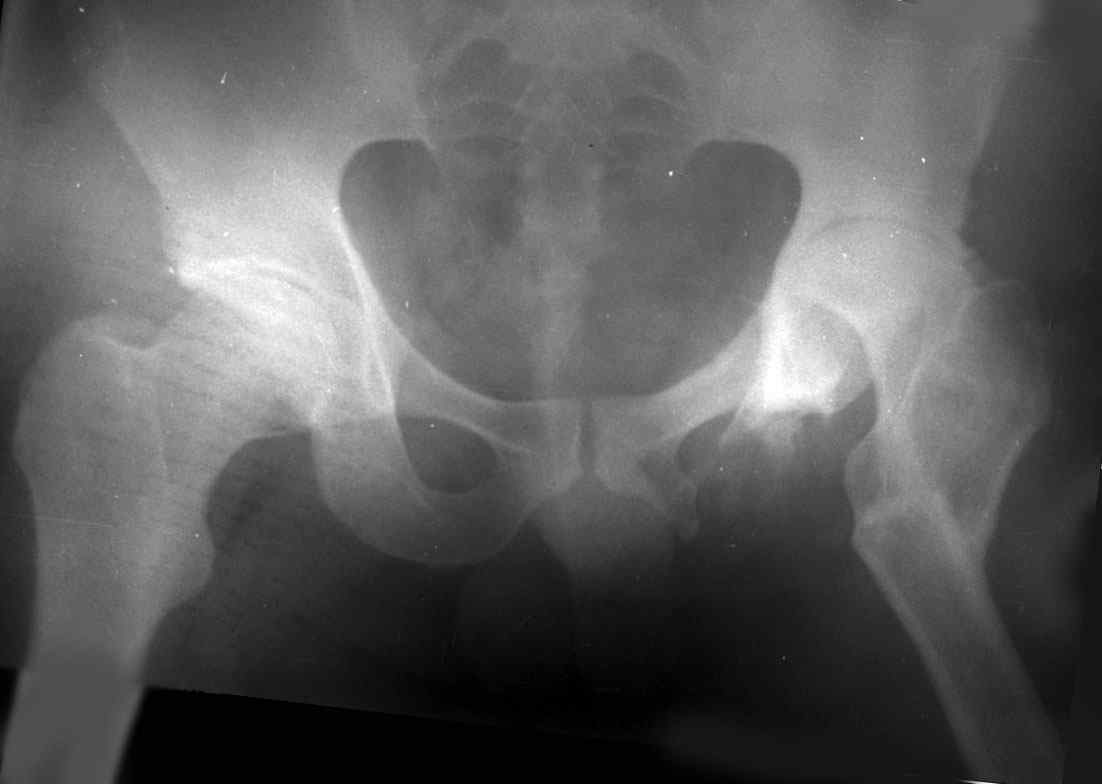

остеотомии. Я представил Р-граммы больных с неудачными р-ми после остеотомий.

Эндопротезирование у них было на порядок сложнее в отличие от артропластики без проведения остеотомии.

Вы немножко не поняли предмета нашего разговора. На представленных Вами Р-граммах речь идет о вальгизирующих остеотомиях, скорее всего в

комбинации с разгибанием... Никто и не оспаривает полезность этих остеотомий, мой личный опыт свидетельствует о том, что даже при

выраженной стадии коксартроза у лиц молодого возраста существенно снижается болевой с-м, ремиссия иногда достигает 12-16 лет, а там уже не

грех и протез поставить.

На обсуждение поставлен вопрос об эффективности опорной остеотомии по Илизарову (как правило), при врожденных вывихах бедра. Почувствуйте разницу...